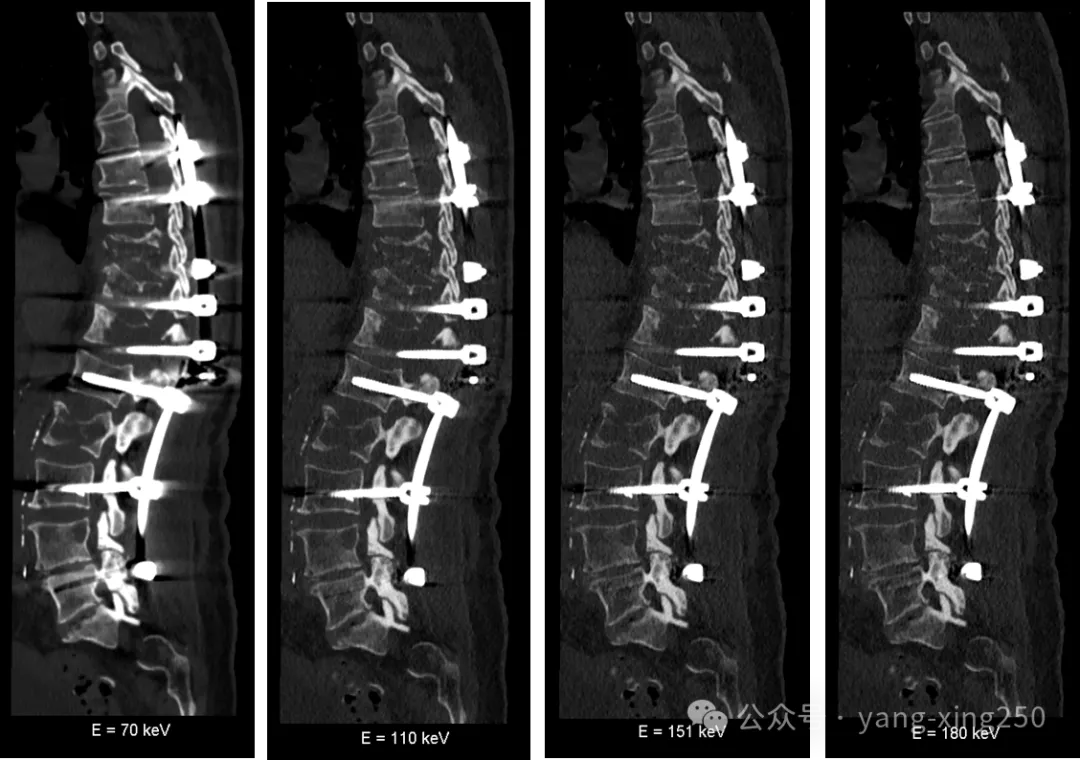

2、单能+(须双能量扫描)

原理:为降低混合能量在通过同一高原子序数金属时,因对不同能量吸收差异被进一步放大而产生的金属伪影;通过双能量扫描,可获得虚拟单能级数据,而重建的虚拟高能级数据在一定程度上具有抑制光子饥饿效应造成的金属伪影。

优缺点:可以回顾重复使用双能数据进行处理;必须进行双能量扫描;在抑制金属伪影的同时亦会抑制其他组织的密度,在临床工作中需权衡;不同材质金属植物,抑制金属伪影的效果不同。

注意:以上抑制金属伪影的方法并非仅能单一使用,在临床工作中,我们可以几种方法组合使用,效果如下:

也有研究表明,iMAR+双能量去金属伪影效果最佳;其次依次为双能量、iMAR。如下图: